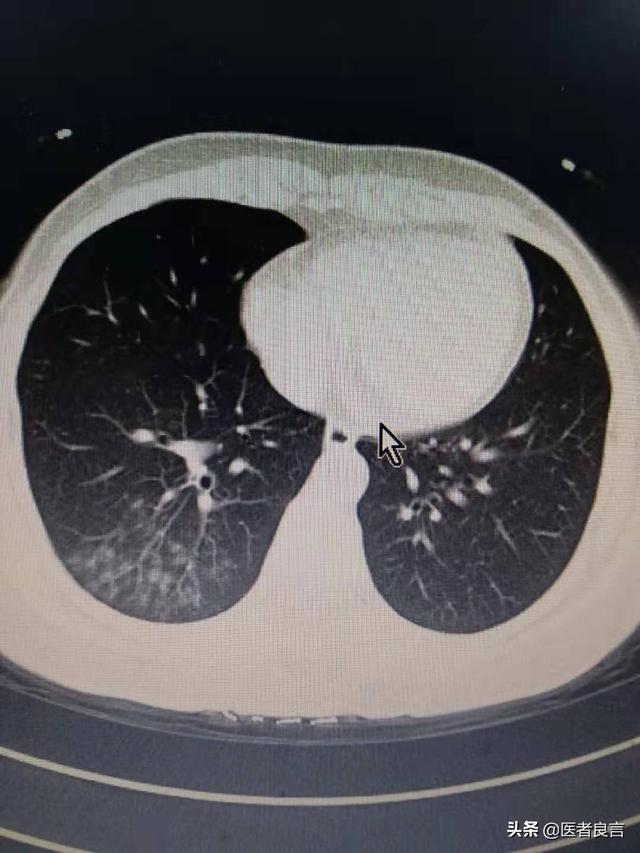

胸部レントゲン写真や肺のCT画像では、肺の外側の帯状に認められる斑状の影や、重症例では肺の固い影が認められることがある。

2.肺炎の画像的特徴を有する:肺に炎症性変化があることを意味し、肺の外側の帯状に明らかな複数の小さな斑状影や間質性変化、さらには両肺に複数の地中影や浸潤影などの変化を示します。ウイルスが肺に侵入した後、肺にうっ血や水腫が生じ、X線やCTで高密度の影が観察されるからです。

②胸部CTを撮影すると、初期には多発性の斑状陰影や間質性変化を示唆することがあり、肺外帯に明らかで、その後の検討で両肺に多発性の地中影や浸潤影が生じ、重症例では固形肺病変が出現する。

②.肺炎の画像的特徴が胸部に認められる。

初期には複数の小さな斑状影と間質性変化を呈し、両肺に多発する地硝子影や浸潤影へと進行し、重症例では肺に固形変化が生じ、一般に「白い肺」と呼ばれる状態になることもある。

2.肺のCTで、地硝子影または浸潤影(CTフィルム上の肺の白い影)を認める。